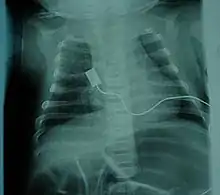

![]() | |

| مکان سلولهای عصبی مبتلا به بیماری در اعصاب نخاعی | |